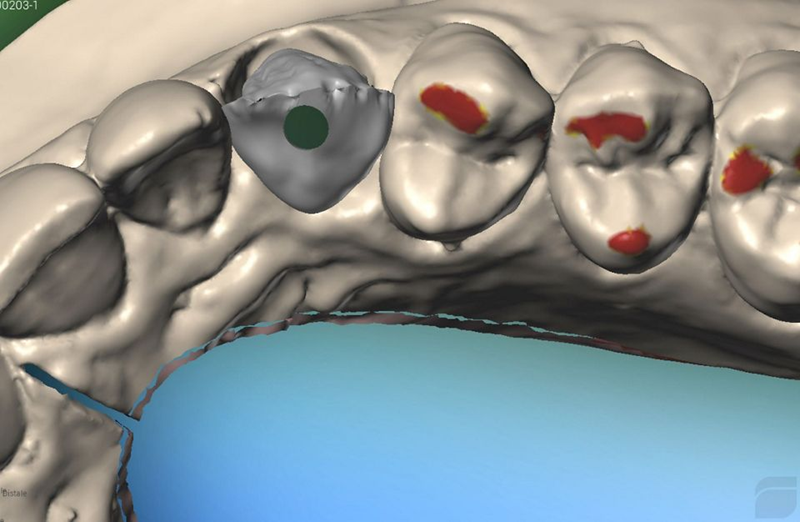

然后,使用 Virtuo Vivo™ 口内扫描仪进行数字印模,并通过此目标将专用扫描体拧在 BLX® 种植体顶部,并将牵引绳放置在牙齿 12 周围以标记线准备(图 1)。 48)。几分钟后,获得该区域的数字印模(图 49)。

Fig. 48: Final digital impression: A dedicated scan body was screwed on top of BLX implant and a retraction cord was placed around the tooth...

Fig. 49: Final digital impression: a screenshot of the data acquisition with the intraoral scanner...

然后,将与印模相关的 STL 文件导入 Dental Wings 实验室建模软件中。种植体虚拟地插入模型中,直径为 3.8 毫米、牙龈高度为 1.5 毫米的 Variobase® RB 放置在其顶部(图 50 a 和 b)

Fig. 50a and b: the STL files related to optical impression were imported in Dental Wings lab modeling software. The implant was virtually inserted...